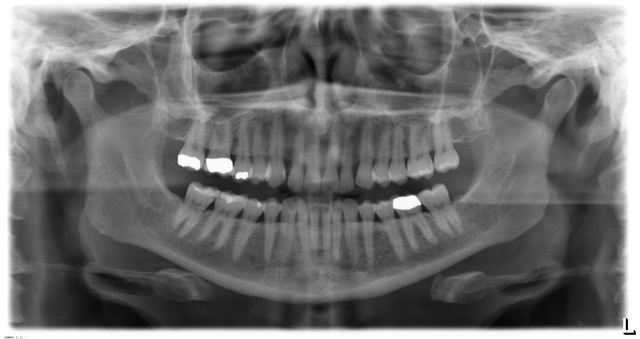

W.C Roentgen discovers X-rays.

• My first crown

I had to get a root canal and two crowns last year because my teeth were getting very weak.